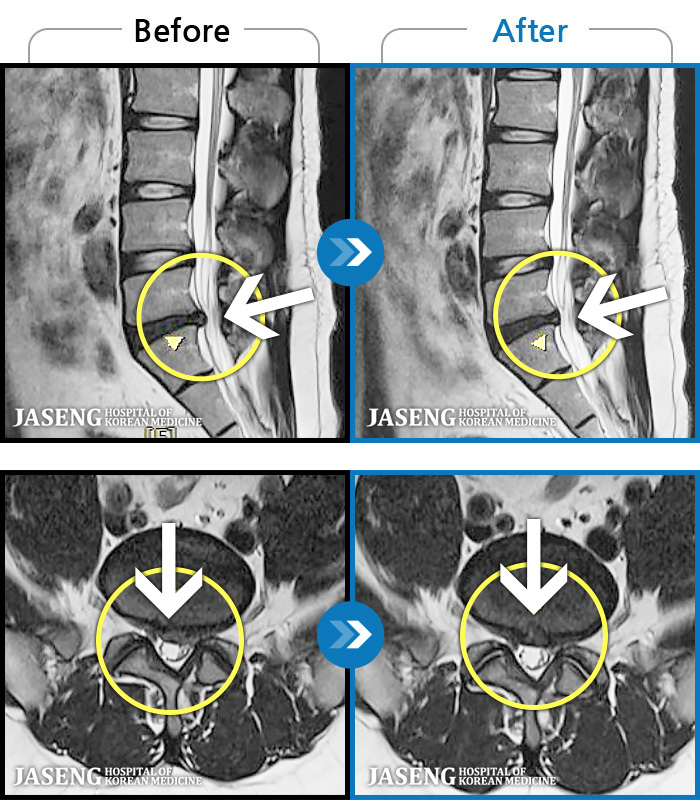

MRI ġ

1,301 MRI ũ ʸ Ȯϼ.